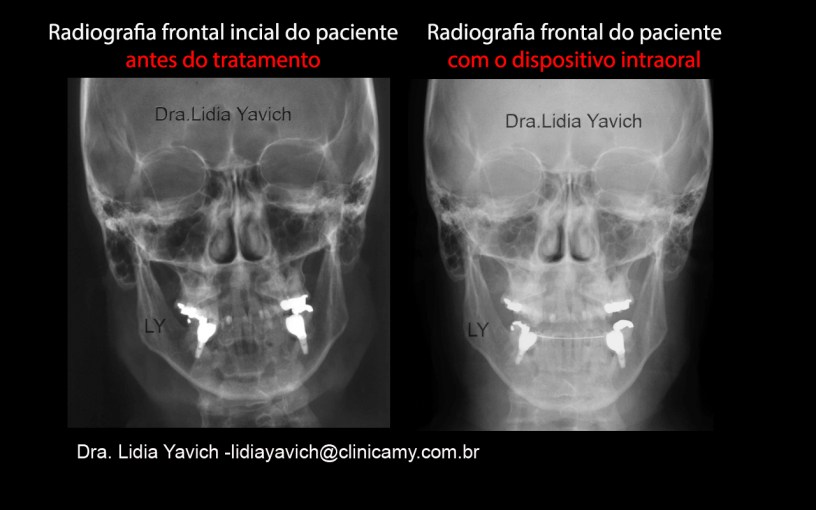

Radiografia panorâmica do paciente antes do tratamento. Radiografia frontal do paciente onde pode ser claramente percebida a impossibilidade de deixar a cabeça em posição reta.

Radiografia frontal do paciente onde pode ser claramente percebida a impossibilidade de deixar a cabeça em posição reta. Laminogafia inicial do paciente, em oclusão habitual onde pode se observar a retroposição das cabeças da mandíbula.

Radiografia Lateral do paciente com o dispositivo em posição neurofisiológica. NOTASSE o espaço entre o arco do ATLAS e o Occipital que não existia na radiografia lateral inicial. Radiografias frontais do paciente comparativas antes do tratamento e com o dispositivo intraoral, o paciente consegue manter a cabeça reta.

Radiografias frontais do paciente comparativas antes do tratamento e com o dispositivo intraoral, o paciente consegue manter a cabeça reta.